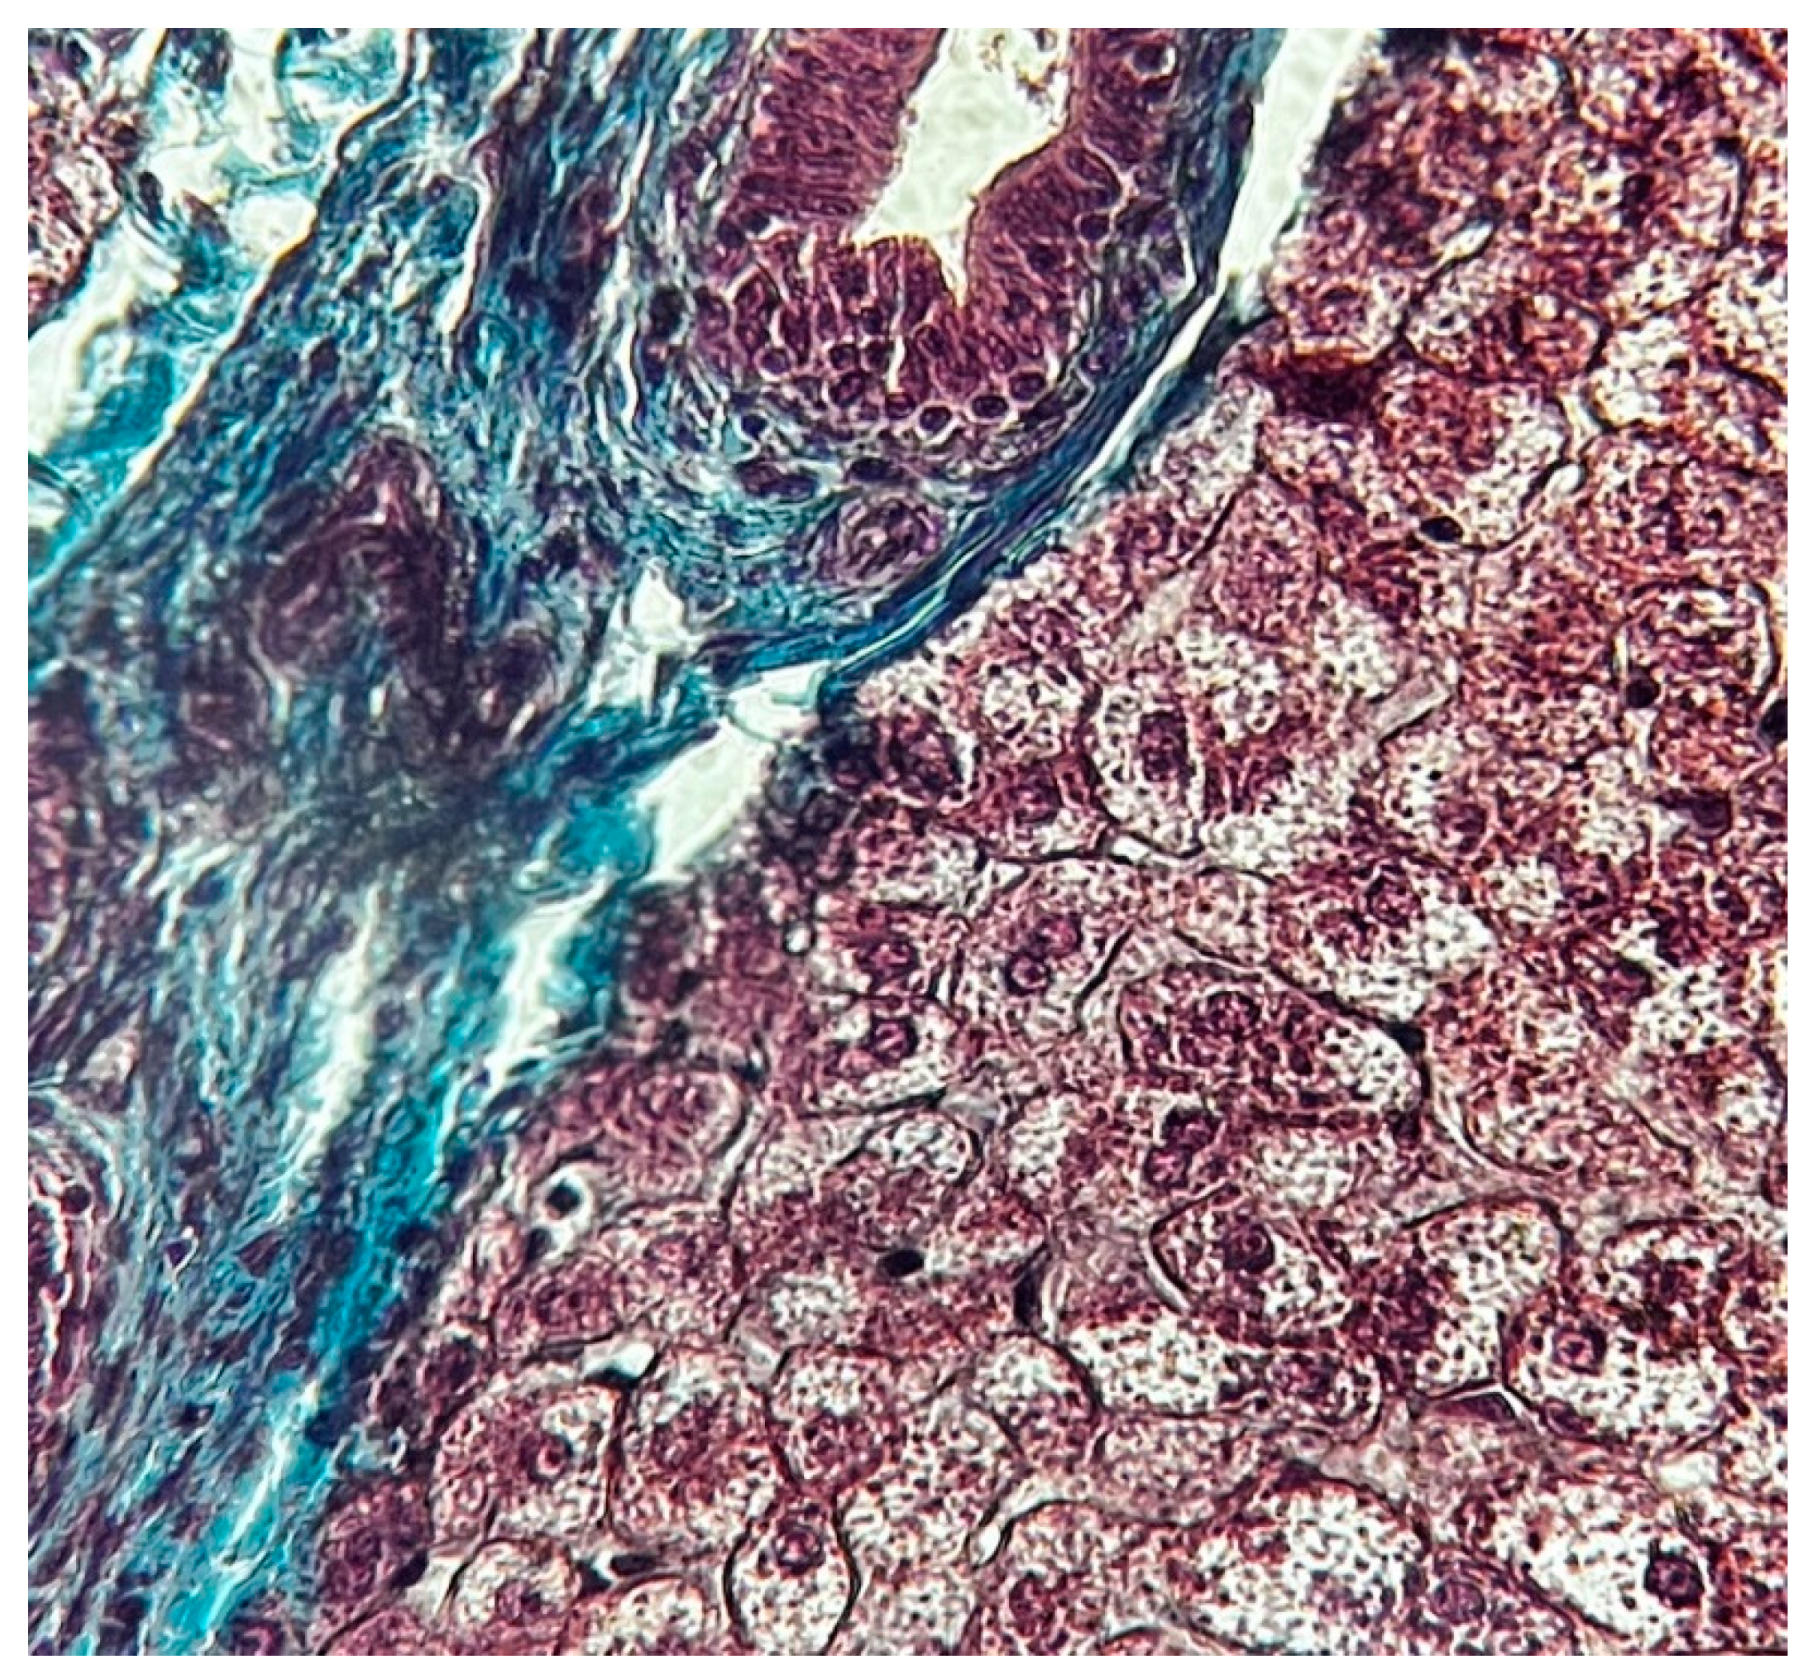

- Zone I is considered to be the periportal region of hepatocytes and are the best perfused and first to regenerate due to their proximity to oxygenated blood and nutrients. Implication in oxidative metabolisms.

- Zone II is defined as the pericentral region of the hepatocytes.

- Zone III has the lowest perfusion due to its distance from the portal triad. Implication role in detoxification.